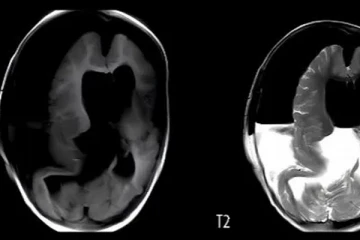

குழந்தையின் தலைக்குள் இருந்த அதன் இரட்டைக் குழந்தை: அதிர்ச்சியூட்டும் ஒரு சம்பவம்